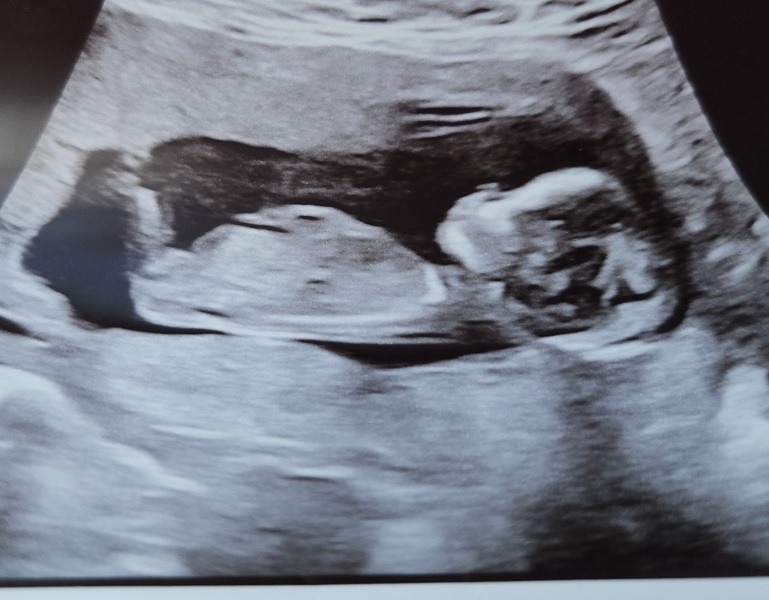

Nub theory anyone?

13 weeks 1 day